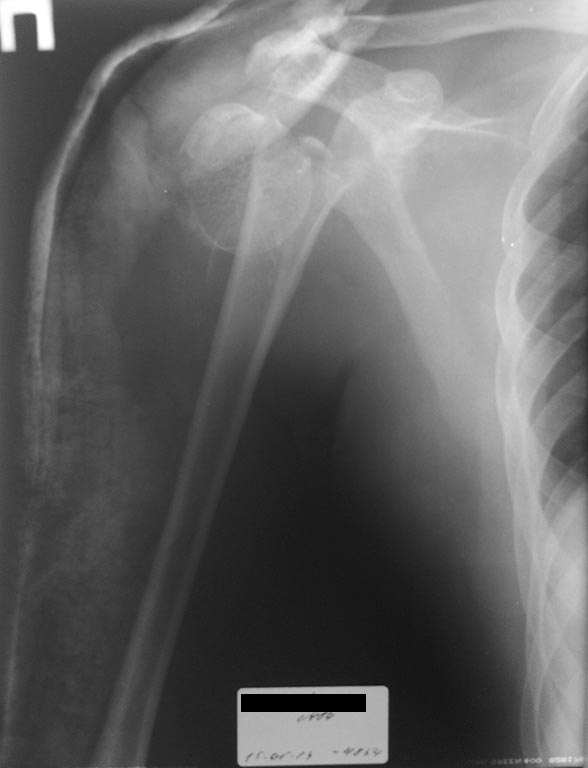

Пациент М, 29 лет, автодорожная травма 10.05.2013, госпитализирован в

ЦРБ. 15.05.2013 переведен к нам. Имеется ЗЧМТ. Ушиб головного мозга.

Закрытый перелом головки и шейки обеих плечевых кости, открытый

многооскольчатый сегментарный перелом костей левой голени (рана по

передне-медиальной поверхности голени в н/з до 2 см).